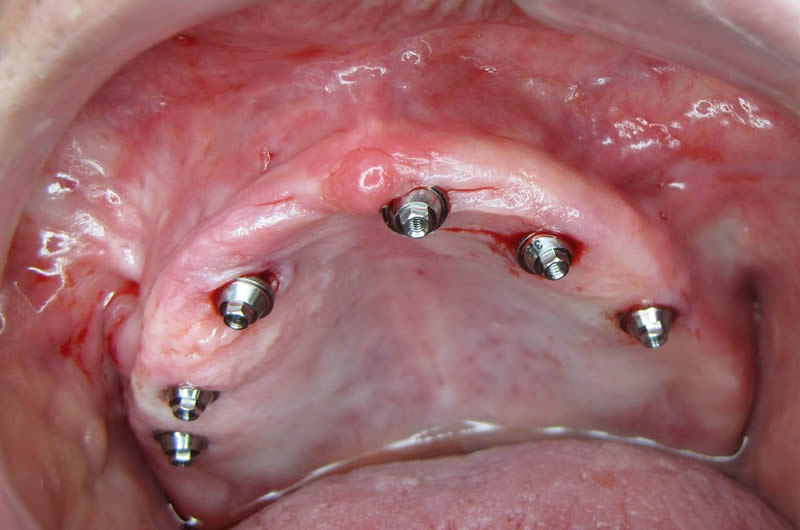

Pós- Operatório Imediato